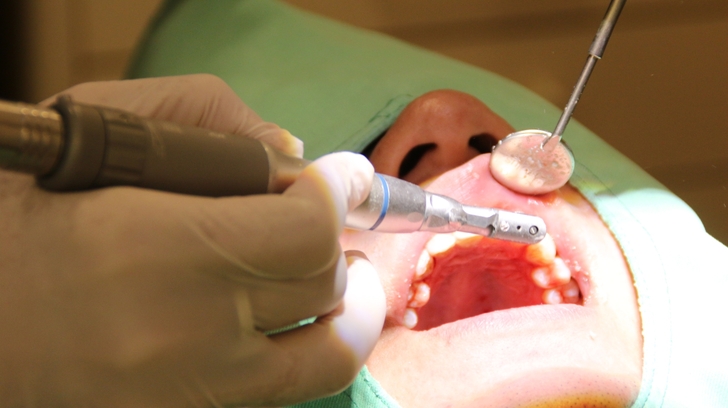

微創植牙手術快速到才躺下十五分鐘時刻,劉醫師竟已迅速完成,過程中因臉部覆蓋著手術巾,加上醫師在牙齦上施打麻醉藥,耳邊除醫師和護士專業術語對話外,麻醉藥上效後竟有些睡意只聆聽到一些敲打聲,嘴裡犯些苦澀,總來不及回神劉醫師已在耳邊說「植牙完成了!再躺一下讓護士替你清潔一下。」